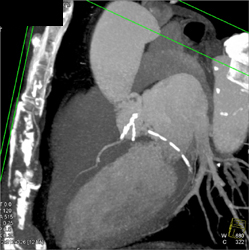

Minimal Plaque in Ramus Intermedius